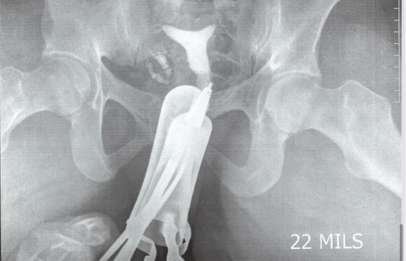

Patient Case Study: Mrs. Zula, 26 – Antai Hospital In this article, we discuss our recent patient case to shed some light on the proper diagnosis and treatment for recurrent miscarriage. Mrs. Zula is a 26-year-old woman from the nation of Zambia, Africa. She had regular 28-day menstrual cycle and was married to the same partner throughout the whole journey.…